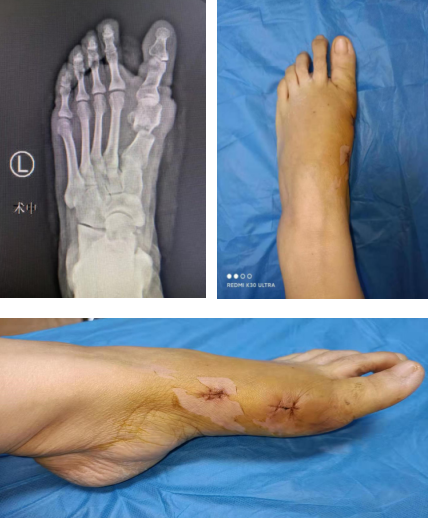

术后外观

术后,李女士第二天就可以下床功能锻炼,曹主任、崔医生医疗组查房查看了李女士足趾的血运情况,曹主任告诉李女士康复情况很理想,一周后就穿着前足免负重鞋下地行走,3个月就自如行走,进行体育运动。